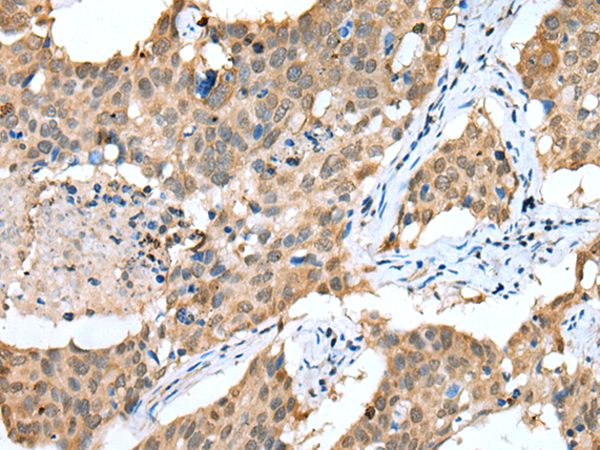

The image is immunohistochemistry of paraffin-embedded Human lung cancer tissue using (SPRY4 Antibody) at dilution 1/25. (Original magnification: ×200)